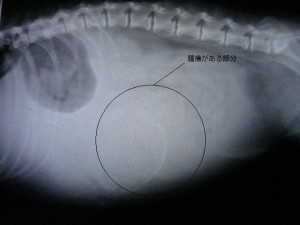

術前のレントゲンです。

腹水が見られ、触診と合わせて腹腔内に大きなmassが認められました。